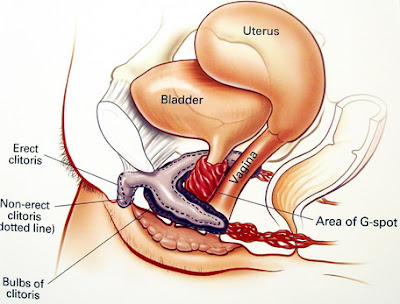

首先来看看下图 Oh My God !!! 这是瞎米?! 我的下体内真的有这庞然大物在里面吗?! ( 7~13公分)

Emily 第一次看到书里介绍时也是非常的惊讶

而事实上阴蒂体确实也如阴茎一样是由海绵体所构成 当妳感到兴奋时,它会充血并像阴茎一样坚硬的勃起

阴蒂脚连着阴蒂体向下延伸,并分裂成两个圆柱状物向两旁伸出

将阴蒂体固定在耻骨位置上,长度约有 5~9公分,在兴奋时它也会充血勃起。

阴蒂球:一样是由海棉体所组成

围绕于尿道上方然后分裂成两个小球分列于阴道两侧

有学者指出:它的作用是在勃起时会撑开阴道让插入更容易些

尿道海绵体: 这部分真的是女性的圣蒂了,它就是俗称的 G点

当女性兴奋时,尿道海绵体会膨胀、勃起,推挤阴道壁

可以感觉到一部分勃起组织这就是所谓的 G点

图中标示为 4 的地方 一直到阴道口附近靠近尿道这边 都可能是 G点所在的位置